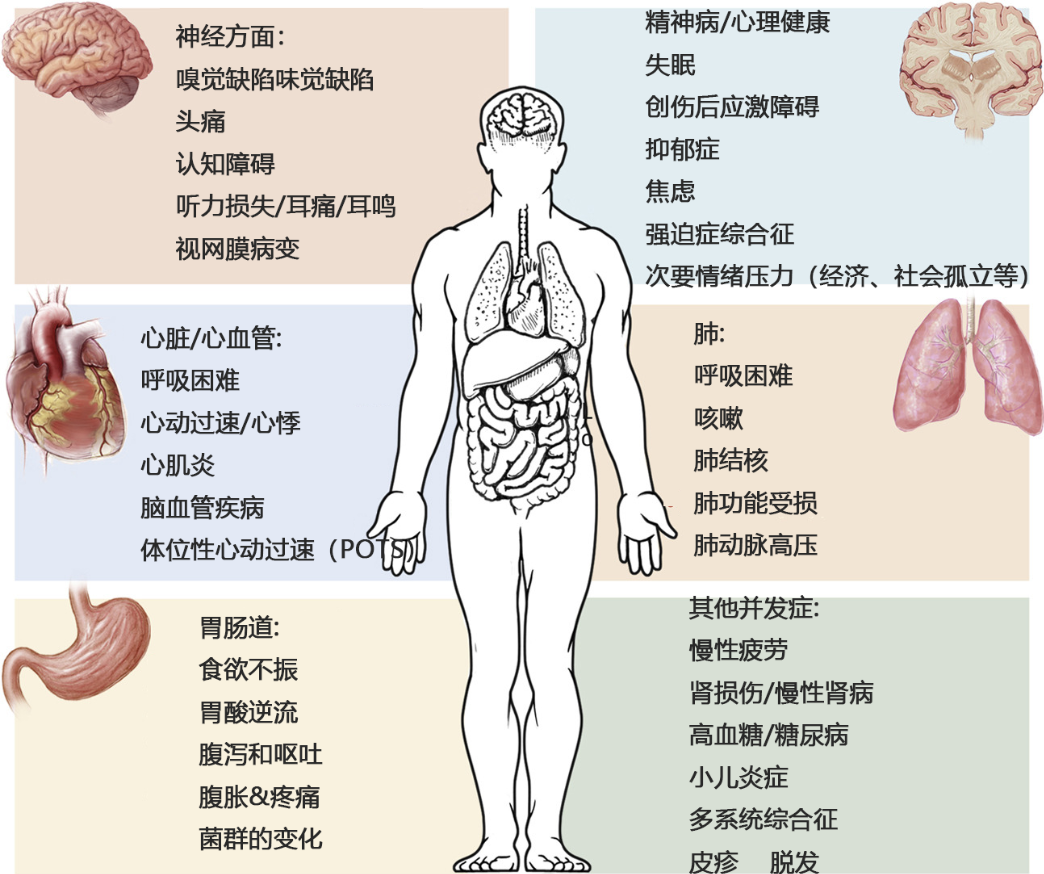

間充質干細胞可改善多種新冠后遺癥

針對新冠病毒對患者多臟器的傷害,全球醫療專家團隊一直在努力探索更有效的康復方式,而有帶著“修復”“再生”光環的干細胞為人類修復新冠患者臟器損傷創造了可能。

研究結果:細胞輸注后,炎癥指標改善,復查胸部CT提示雙肺病灶較前吸收,呼吸道癥狀改善,新型冠狀病毒核酸檢測連續2次陰性,治愈出院。